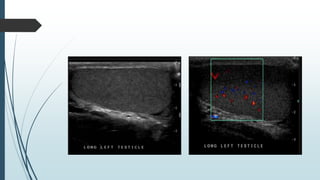

Hypoechoic area with heterogenicity noted

on right testis.

Colour dopplar.

Normal left testis of same patient.